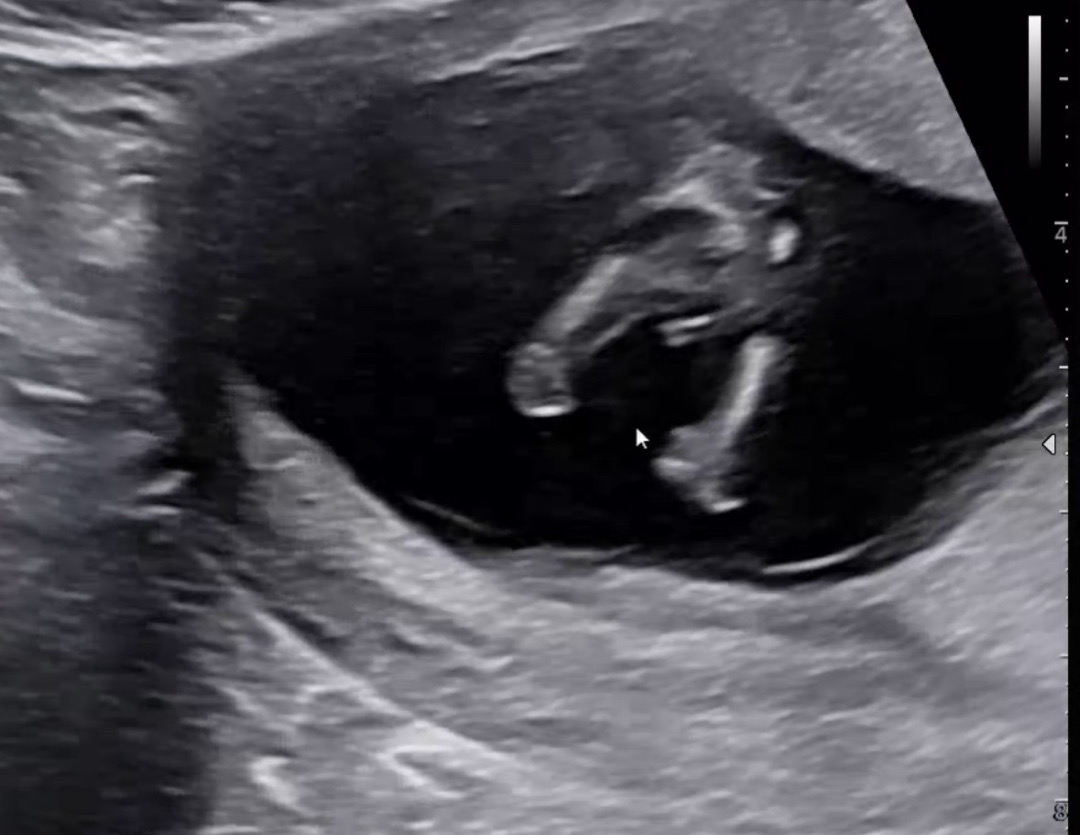

12주 5일 초음파인데 영상으로 보면서 계속 뭐가 보여서 아들이냐 여쭈니 대답은 안해주셨는데 걍 누가 봐도 아들이지요...?

저때는 다 저모양이라거 하셧어요 저희 선생님은 각도법으로 봐주시더라고요 ㅋㅋ